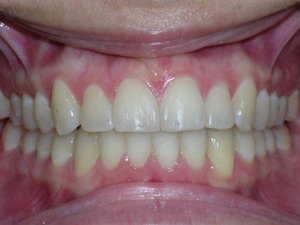

Here are the results. We used a bonded retainer on the bottom teeth.

Hope you like it too!